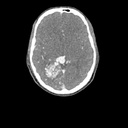

Dieses Phantom ist aus echten Patientendaten erstellt und wird mit neuester Technologie hergestellt. Knochen, Gefäße und Weichteilgewebe werden authentisch dargestellt mit realistischen CT-Werten für alle Gewebe bei 120 kVp Röhrenspannung in der CT. Wenn das Phantom vorwiegend bei anderen Röhrenspannungen (z. B. 100 kVp) eingesetzt werden soll, kann die Kalibrierung der CTWerte auf Wunsch entsprechend angepasst werden. Das Phantom liefert realistische Gewebekontraste in der Röntgen-Bildgebung. Lufträume sind durch ein Material mit etwa -80 Hounsfieldeinheiten aufgefüllt.

Das Kopf - Phantom liefert eine äußerst realistische Simulation einer Kopf- und Hals-CT-Angiographie (mit arterieller Kontrastierung) eines Patienten mit einer arteriovenösen Malformation auf der rechten Seite. Das Phantom wird in originalgetreuem Maßstab geliefert und beinhaltet die Halswirbelsäule bis zur Grundplatte des fünften Halswirbels.